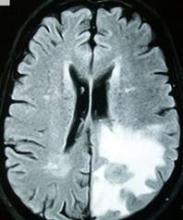

Courtesy Bobjgalindo/Wikimedia Commons/Creative Commons License

A brain tumor, the first cancer to strike the late Senator Arlen Specter.

According to the definitive obituary in the Philadelphia Inquirer, his hometown paper, Sen. Specter, who died on Oct. 14 at age 82 from complications of non-Hodgkin’s lymphoma, first was stricken by cancer in the form of a brain tumor in 1993 (when he would have been about 63). After that came diagnosis and successful treatment of a second brain tumor in 1996, and treatment for Hodgkin’s lymphoma in both 2005 and 2008, followed by the non-Hodgkin’s cancer that led to his death.